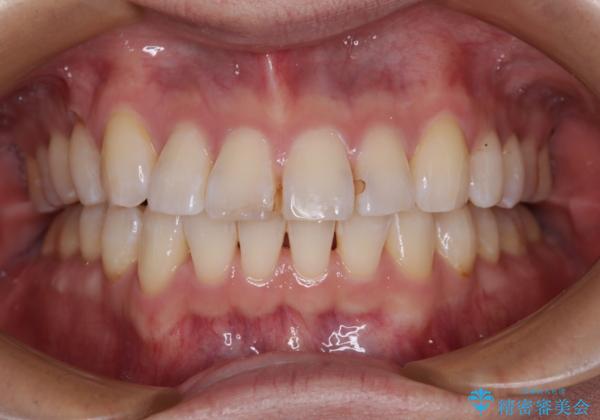

- 以前矯正治療を行ったものの、思い通りの仕上がりではなく、更には後戻りが気になってきたとのことで来院された患者様です。

上顎右側の第一小臼歯が動きにくい歯であり、以前矯正治療を行った際に傾斜した位置のまま終了したことと、それに伴い後戻りで歯列が波打っているようになっていることを大変気にしていらっしゃいました。

咬合平面改善のため、アンカースクリューを多用し、ワイヤー装置にて矯正治療を行うこととしました。

動きにくい歯はやはり動きにくく、咬み合わせ改善に時間を要しましたが、患者様には大変満足していただけました。